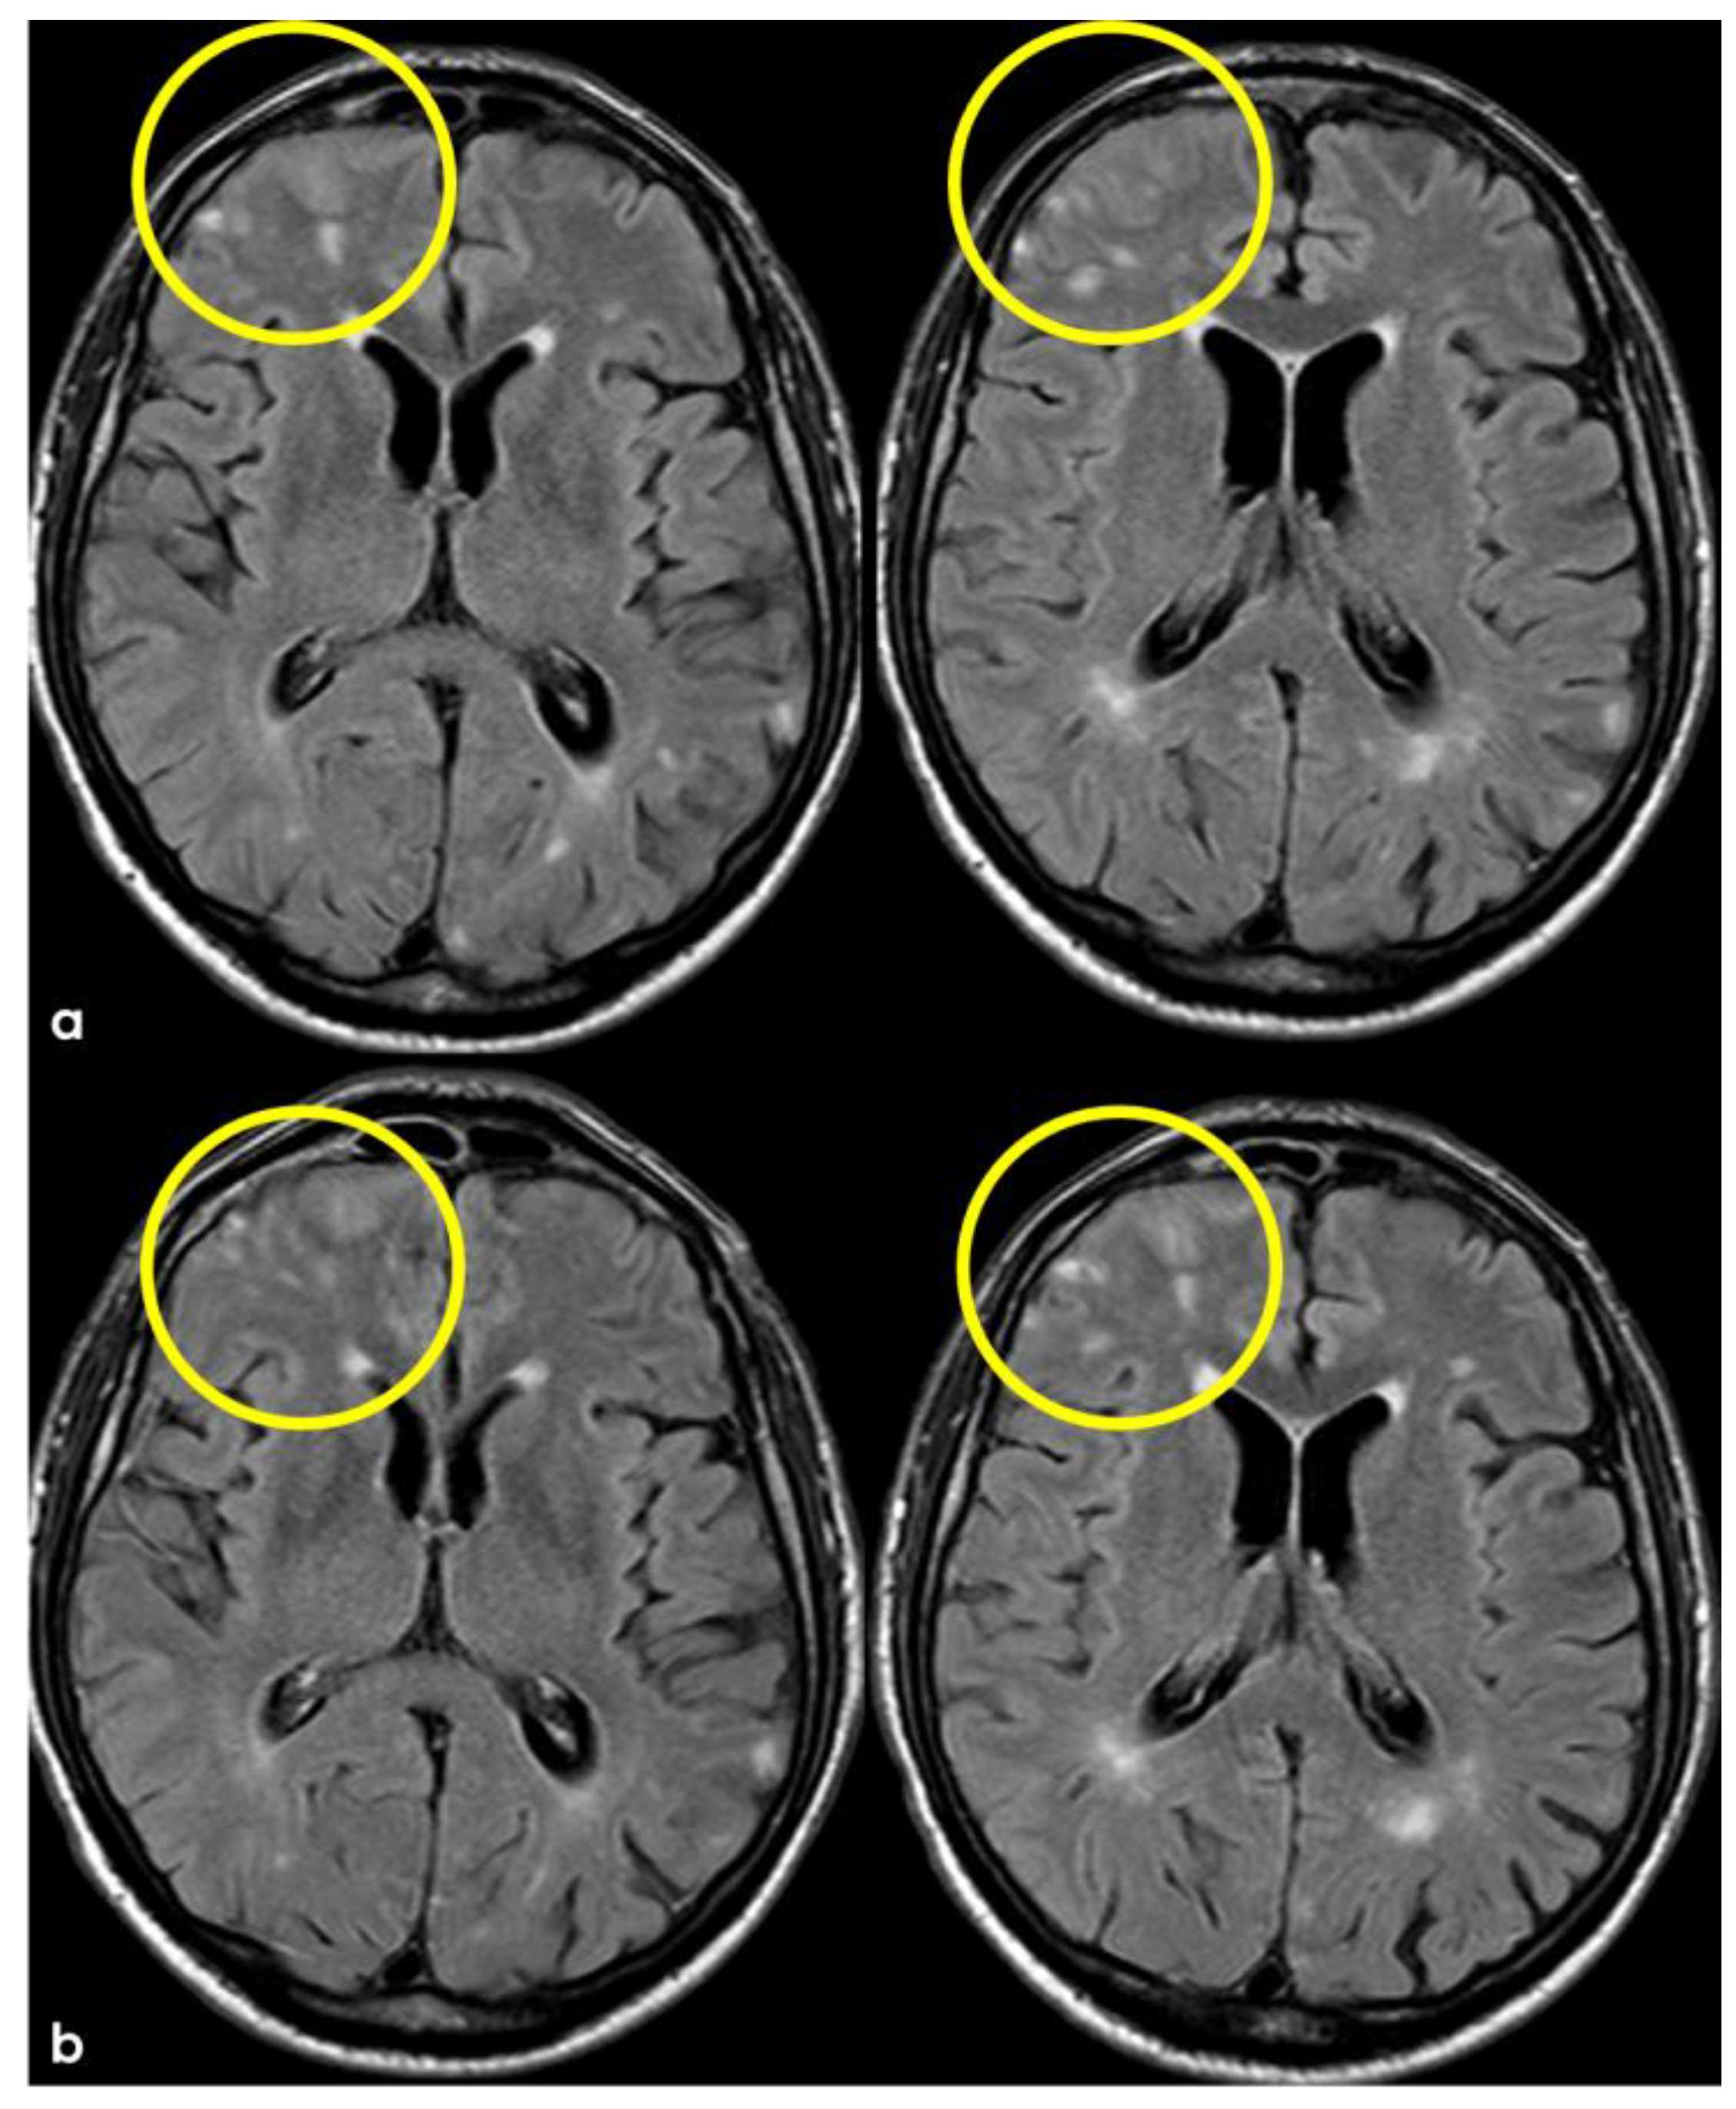

5. February 2017: First Recurrent CAA-Related Inflammation